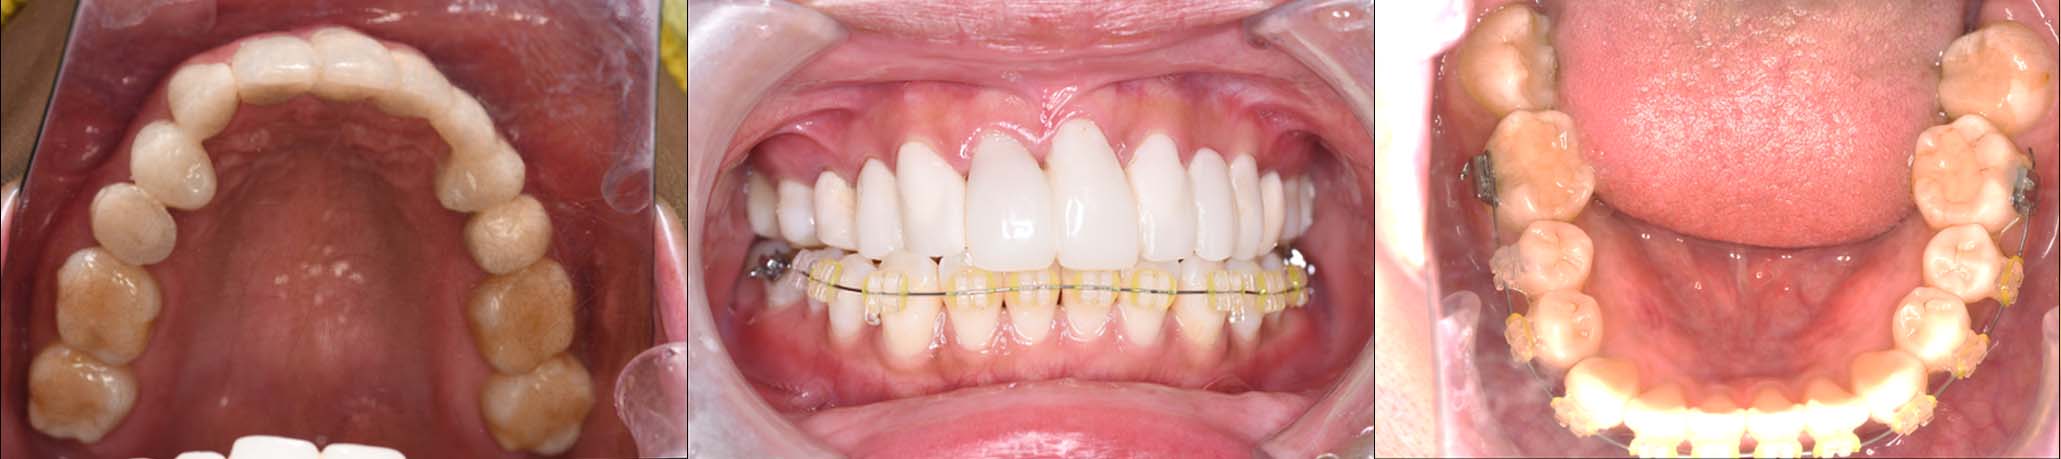

2024年 10月 下顎MTM開始

2024年 10月10日

10月21日

11月7日

11月28日

12月16日

12月23日

1月9日

1月30日

2月20日

3月13日

4月24日

9月25日